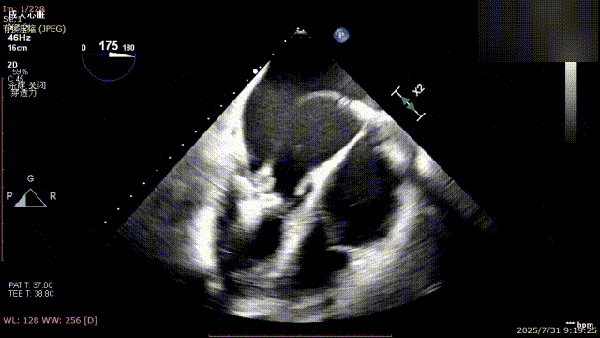

术前完善经食管超声评估,提示该患者双房大,二尖瓣重度反流4+伴后叶脱垂、后叶部分腱索断裂。根据评估结果,心脏大血管外科王安彪主任团队制定了周密的手术方案:植入一枚夹合器,钳夹P1区反流最大处,尽可能夹持全部后叶脱垂瓣叶组织,后续根据术中实时残余分流和跨瓣压差等指标,并依据实时超声监测调整治疗策略。

三维评估;二尖瓣P1脱垂偏心性返流

术前影像